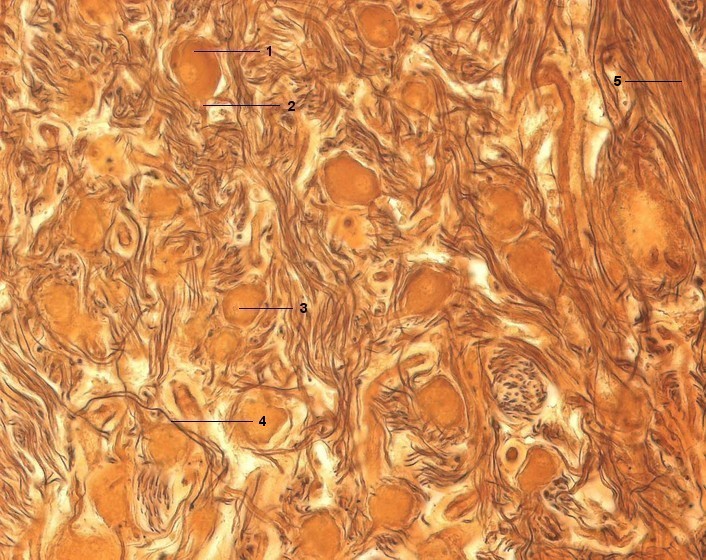

1 Multipolare Nervenzelle, Perikaryon

2 Nervenzelle, Dendrit

3 Zellkern mit Nukleolus

4 Nervenzelle, Axon

5 Nervenfaserbündel